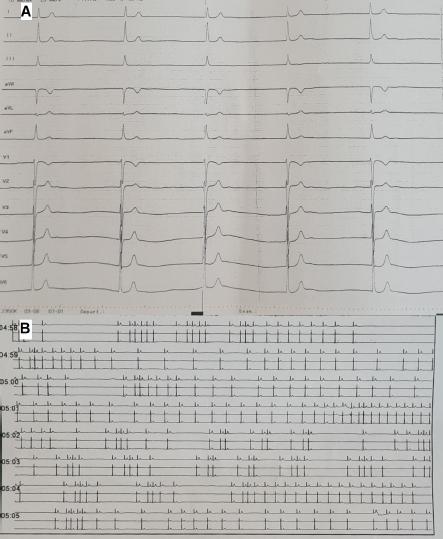

Figure 1

A. The presenting ECG showed a junctional rhythm with a narrow QRS complex at 30 bpm with no atrial activity. B. The 24-hour Holter ECG monitoring showed numerous ventricular pauses and no atrial activity. ECG – electrocardiogram.

Figure 2

Intracavitary electrograms (49mm/s) showed no atrial capture during pacing at 600 ms, 20mA at 1ms pulse duration at the level of the right atrium (quadripolar catheter at the lateral wall of the RS, the electrogram marked His d) (A) and coronary sinus (decapolar catheter placed in the coronary sinus, the electrogram marked CS 5-6) (B).